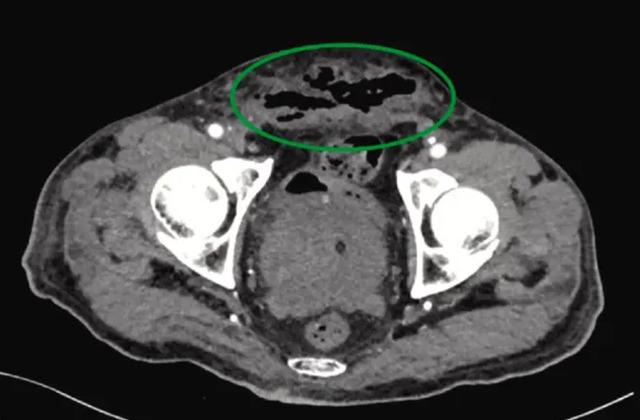

The Sun gazetesinin yayınladığı habere göre, aşırı alkol tüketimi nedeniyle hastaneye kaldırılan bir adamın tomografisinde, büyüyen prostatında bol miktarda gaz içeren apse olduğu görüldü. Ayrıca “üretra ve sünnet derisi, skrotum ve rektal parmaklardan bol miktarda cerahatli, yeşilimsi ve kötü kokulu akıntı” kaydedildi. Penisin tamamen siyah ve çürük olduğunu gören doktorlar, hastaya “tam penis nekrozu” uygulamak zorunda kaldı. Hastanın ameliyata razı olduktan sonra penisi kesildiğinde herhangi bir dokuya rastlanmadı.